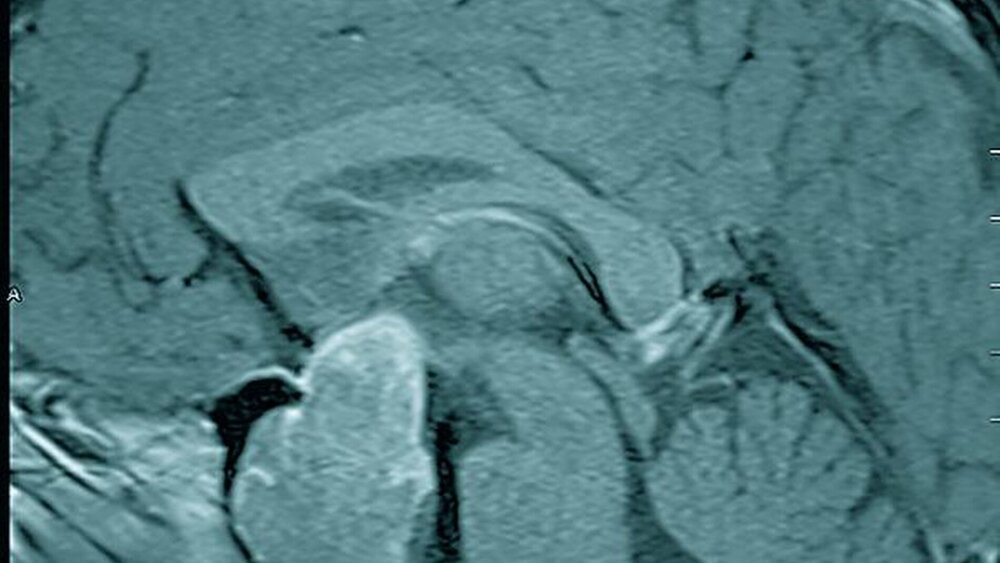

Das angefertigte Fernröntgenseitbild ließ eine massive mandibuläre Prognathie, prominente Supraorbitalwülste und eine stark vergrößerte Sella turcica erkennen (Abbildung 6). Aufgrund des Verdachts einer Akromegalie wurde eine Magnetresonanztomographie veranlasst, in der sich ein intra- und supra sellärer Hypophysentumor von 4,7 x 2,9 x 2,2 cm3 Größe darstellte. Zudem untermauerte eine deutliche Verdickung der gesamten Schädelkalotte die Diagnose Akromegalie (Abbildungen 7 und 8).